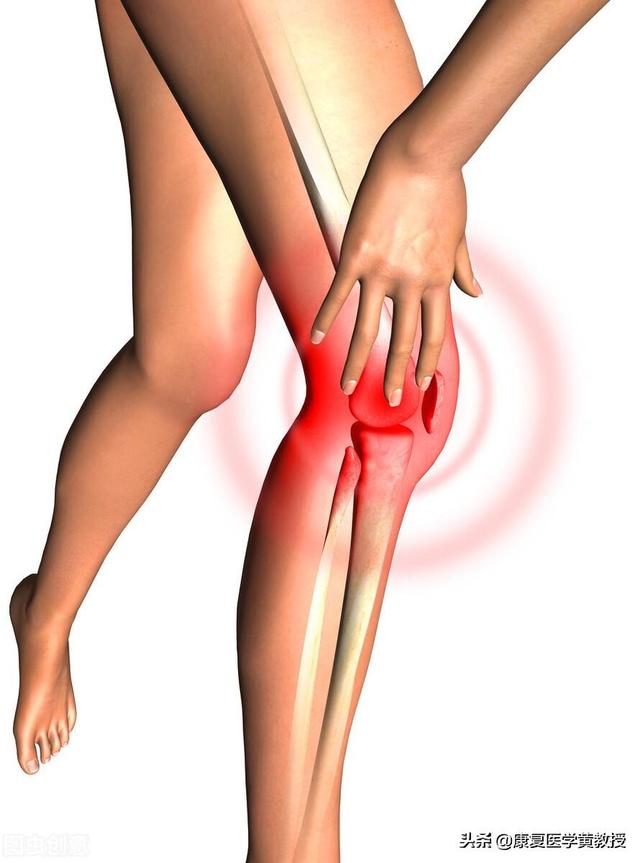

初期の変形性関節症患者は、しばしば以下のような症状を示す。膝裏の張り。であったろう。関節の弱さ特に、次の試合がある場合は。弱った足を叩くこの病気の症状として、しゃがんだ時に明らかに関節がポキポキと鳴り、痛みを伴う患者もいる。病状が重くなるにつれて、患者さんの症状はより重くなり、一部の患者さんでは徐々に階段の上り下りや平地を歩くときに関節が痛む。さらに重症になると、安静時にも関節痛が出現し、著しい痛みを伴うこともある。関節可動域障害および関節の変形。

中年女性の方が膝関節痛の発生率が高いようですが、男性の活動レベルが高いことや、サッカーやバスケットボールなど膝関節に大きな負担をかけるエキサイティングなスポーツを好むことなどから、巨視的に見ると、膝関節の使い過ぎと膝関節損傷の可能性との間には、非常に微妙な関係があるとされてきました。臨床症状によると、中高年の女性は軟骨のすり減りや半月板の損傷、骨棘ができやすいのに対し、男性は靭帯の損傷や半月板の損傷が多く、骨棘ができにくい。これは、一般的に男性の骨が女性よりも硬いためと考えられる。

筋肉は骨を守る「鋼鉄のケーブル」である。筋肉は力を失い、骨には過負荷がかかる。筋肉が力を失うと、骨に過負荷がかかり、特に以下のような多くの問題をもたらすことになる。膝関節のように重い骨にとって、脚の筋肉の強さは非常に重要である。。

上の図では、筋肉と腱が協力して膝関節を保護していることがわかる。一般的に言って膝から上のこの2つの筋肉が著しく縮むことは、膝の問題とは程遠い。

筋肉に加えて、血行の問題もある。膝関節の栄養は血管と末梢神経系から供給される加えて、高齢、血液循環の悪化、末梢神経系の変性を引き起こす基礎疾患があると、膝関節への栄養供給に影響を及ぼし、問題を引き起こす可能性がある。